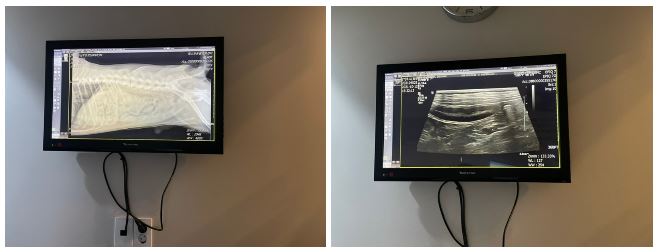

엑스레이만 찍어보기로 했어요

저는 아무것도 모르지만

확실히 뭐가 걸린건 없어보였습니다

근데 장쪽에 살-짝 염증이 있더라구요

다행히 목에 걸리거나, 식도나 기관지쪽에는 문제가 없었고

장 윗부분에 살짝 장염이 있었다고 하네요

근데..뚜니 위를 보시고는 아가가 아침을 많이 먹었는지

위가 좀 비대해져있다고 하시길래